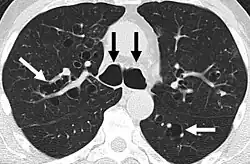

A chest X-ray is abnormal in most patients with bronchiectasis. Computed tomography is recommended to confirm the diagnosis and is also used to describe the distribution and grade the severity of the disease. Radiographic findings include airway dilation, bronchial wall thickening, and atelectasis.[65] Three types of bronchiectasis can be seen on CT scan, namely cylindrical, varicose, and cystic bronchiectasis.[66]

- Bronchiectasis primarily in the middle lobe of the right lung.

- Bronchiectasis secondary to a large carcinoid tumor (not shown) that was completely obstructing the bronchus proximally. Dilation of the airways is present.